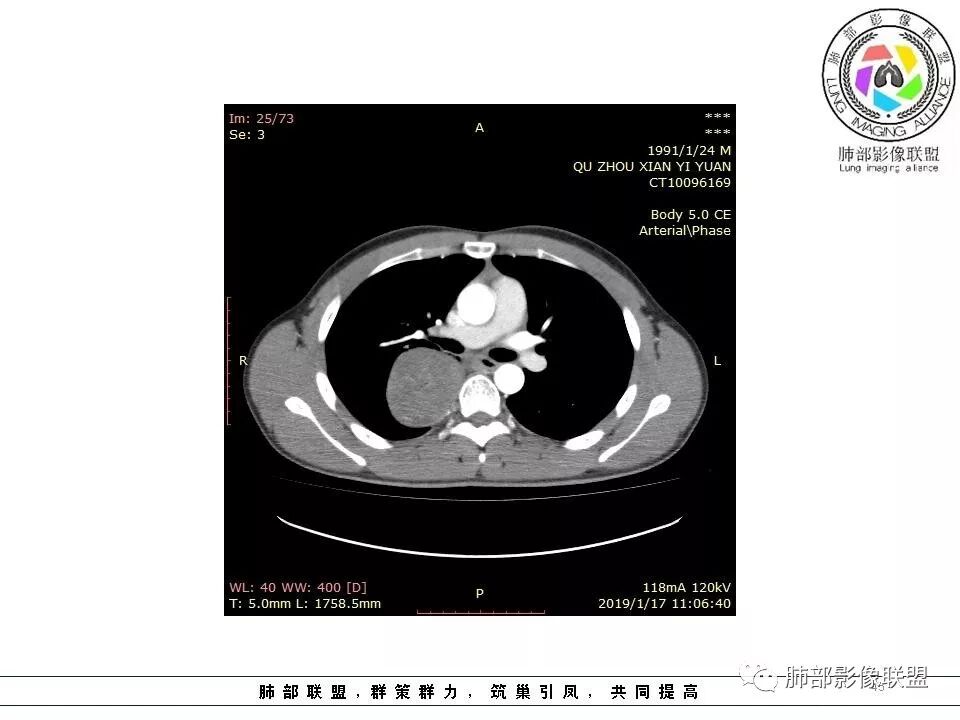

青年男性,右侧脊柱旁软组织肿块,边缘膨隆,密度不均,临近肺组织受压、胸膜增厚,增强后动脉期呈不均匀强化,并可见肋间动脉供血,延迟期强化较均匀,定位肺外,首先考虑SFT,神经源性肿瘤待排

青年男性,右侧后纵膈肿块,有胸膜尾征,支气管被推压,定位肺外,脏胸膜?血供来自肺动脉及肋间动脉,增强后有强化,蛇纹征,考虑SFT,鉴别鞘瘤

右侧后纵膈肿块,有胸膜尾征,周围肺组织及支气管被推压,定位肺外,脏层胸膜来源,血供来自肺动脉或者支气管动脉,增强后持续渐进强化,蛇纹征,考虑SFT,鉴别鞘瘤。

青年男性,右后上纵隔脊柱旁沟可见团状软组织影,边界清,密度尚均匀,推挤邻近肺组织,胸膜可见掀起,有肺动脉供血,增强轻度蛇皮样强化,纵隔淋巴结未见肿大,邻近骨质未见破坏,胸膜下脂肪间隙消失,考虑SFT孤立性纤维瘤可能性大,鉴别神经鞘瘤,节细胞瘤,建议活检。

青年男性,胸痛,右上纵膈脊柱旁肿块,形态光整规则,支气管被推移,临近的胸膜明显增厚,有胸膜掀起,增强后密度不均匀,可见蛇形血管征,血供似乎有两根血管供血,考虑SFT

右上肺野脊柱旁软组织肿块,边缘光滑整齐,肺组织及气管右肺上叶支气管受压前移,外移,边缘可见胸膜尾征,病灶内密度不均,增强后渐进性持续强化,其内可见明显蛇纹血管征,首先考虑肺外来源,sft.可能性大

青年男性,右侧脊柱旁占位,瘤肺界限清晰,支气管推移,胸膜尾,D字征,胸膜下脂肪影,蛇纹血管,双重供血,延迟强化,定位胸膜,支持sft

脏层胸膜主要由支气管动脉和肺动脉供血,壁层胸膜主要由支气管动脉,胸廓内动脉、肋间动脉供血

如果是肋间动脉,就不可能是脏层胸膜,可以是壁层或者纵膈

但是这个病人,肋间动脉供血吧,我倾向胸膜

边缘光滑,宽基底与胸壁相连,跨叶裂,叶裂稍前推,血管、支气管前移。

浅分叶

外上侧少量胸水

肋间动脉供血,强化尚均匀,逐步强化